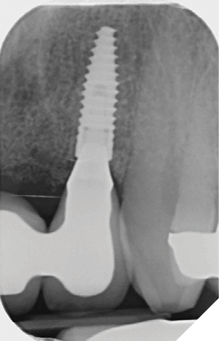

Radiographic examination shows the upper left lateral incisor tooth has decayed through and through and the upper right central incisor tooth is heavily root treated and filled (Figs. 1-2).

Fig. 1

Fig. 2